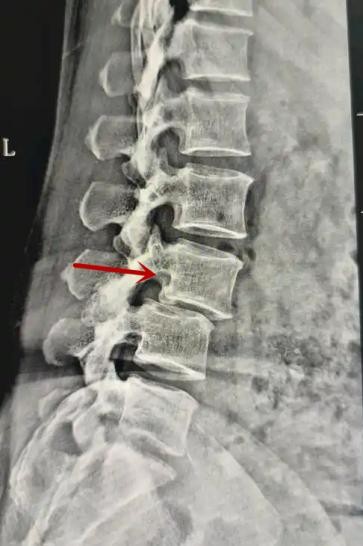

利器一:X線/DR

腰椎X線片作為最基礎(chǔ)的影像檢查手段,利于X線穿透人體組織后成像,以其快捷、直觀、價格低廉的特點,X線檢查主要包括腰椎正側(cè)位、雙斜位以及過伸過屈位。主要用于觀察腰椎骨骼的情況,如椎體是否有骨折、骨質(zhì)增生程度、生理曲度的變化、椎體移位的情況等。然而,X線檢查也有它的局限性,無法判斷是骨折的新舊,對于椎體內(nèi)部結(jié)構(gòu)和周圍肌肉韌帶組織(如脊髓神經(jīng)、椎間盤、韌帶等)的顯示不佳,另外X線作為有輻射檢查,孕婦及嬰幼兒謹慎選擇。

箭頭提示腰1椎骨折